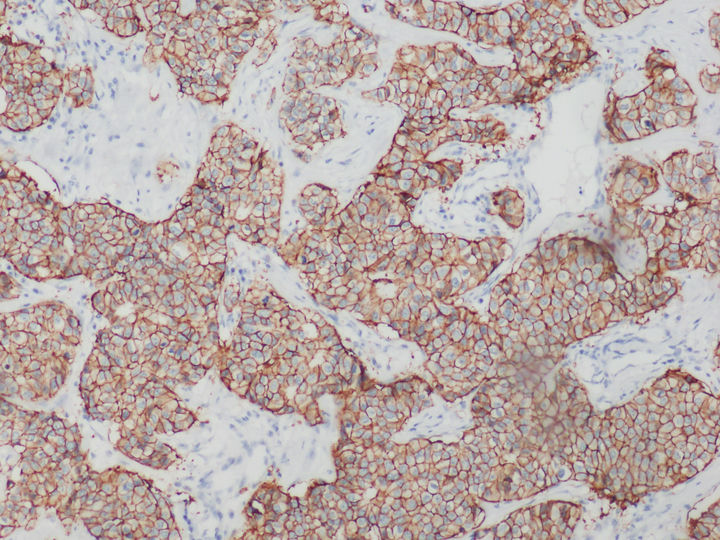

荧光显微镜下的乳腺癌HER2检测

HER是一类与细胞增殖息息相关的蛋白质,全称是human epidermal growth factor receptor,中文叫作人表皮生长因子受体。HER蛋白质家族共有四兄弟,其中HER2负责将细胞膜外的生命信息传导至细胞内,是乳腺癌诊断指标之一,检测HER2一般用正置荧光显微镜,使用免疫组化或荧光原位杂交FISH技术。

在乳腺癌,胃癌等肿瘤筛查领域中,HER2的表达水平是肿瘤检测的常用指标。目前,HER2基因检测常见方式以免疫组化IHC技术和FISH技术为主。

免疫组化HER2检测可以用普通显微镜明场观察实现,设备要求较低,但灵敏度和特异性相对弱。